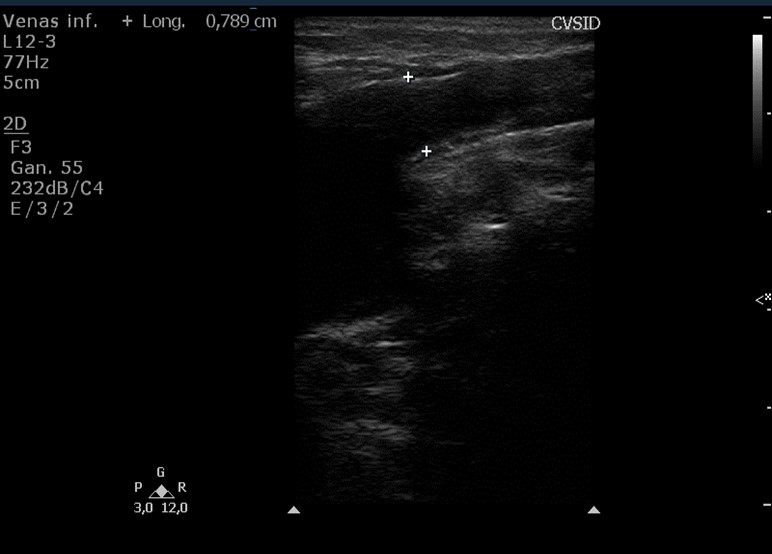

Sistema de venas perforantes. Son vasos de un diámetro que no debe superar los 3 mm. Atraviesan la aponeurosis muscular y comunican el sistema venoso superficial con el sistema venoso profundo, mediante un sistema valvular que en condiciones normales permite el drenaje de sangre en ese sentido. La forma de cono truncado, con el orifico externo menor que el interno favorece direccionar el flujo desde el sistema superficial al profundo (4) (Fig. 3 y Fig. 4).

El reflujo fisiológico, que se ve representado como inversión del color o de la onda de Doppler pulsado, no debe superar un segundo en el sistema venoso profundo y el cayado safeno-femoral, y los 0,5 segundos en el sis-tema venoso superficial. Los diámetros venosos deben ser como máximo de 6 mm en topografía suprapatelar y de 3 mm infrapatelar, y las venas perforantes no deben superar los 3 mm.